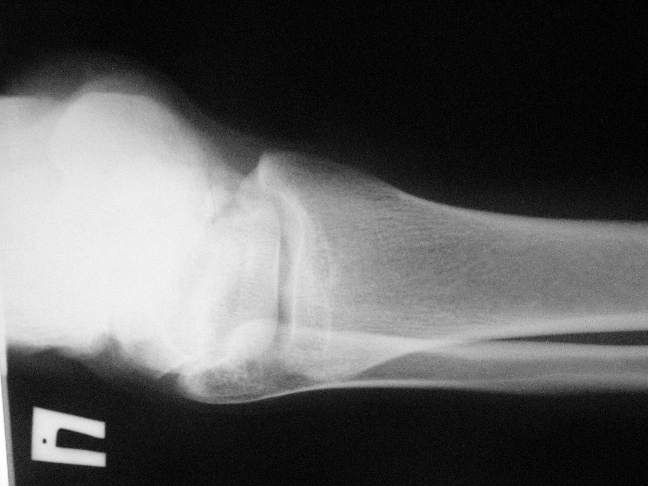

Справа перелом таранной кости со смещением  и мыщелка бедра без смещения,

посылаю дополнительные проекции.